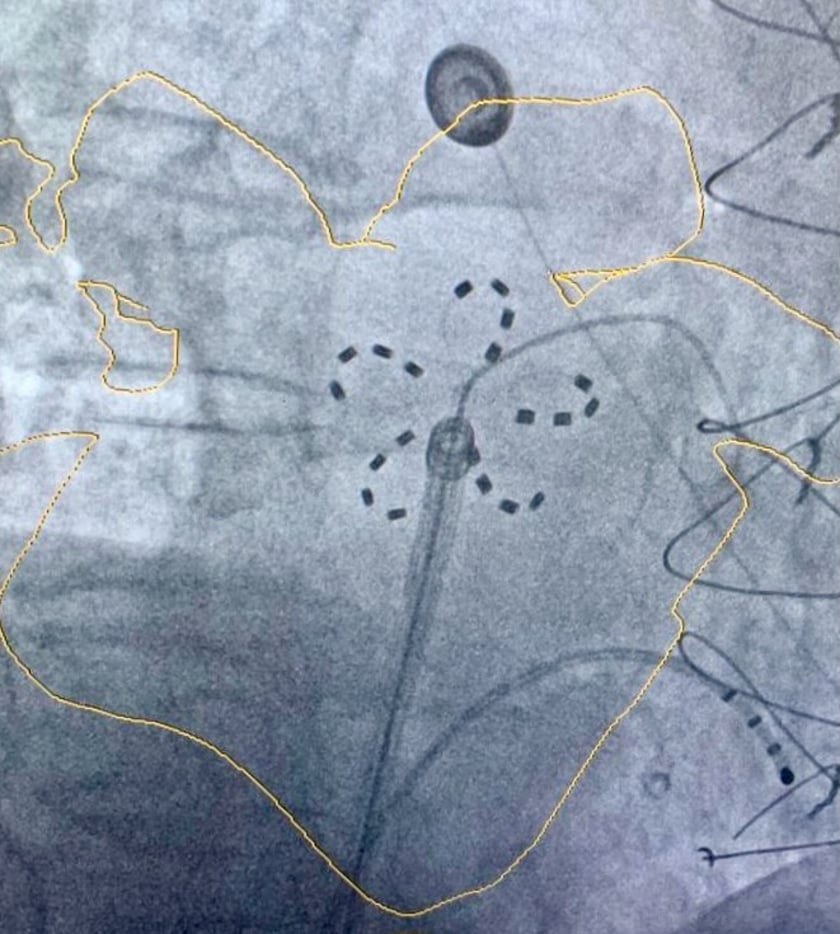

<p>Elektroda ablacyjna widoczna we fluoroskopii</p> USK

Elektroda ablacyjna widoczna we fluoroskopii